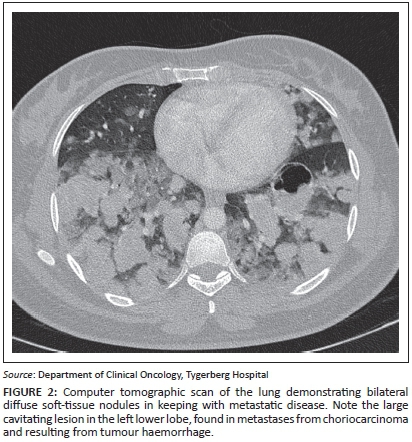

A 20-year-old woman (gravida 2, para 0, miscarriage 1) presented with a history of haemoptysis, grade IV dyspnoea and a raised B-HCG level. She was known to have had a previous molar pregnancy, diagnosed three years previously. On clinical examination, symptoms and signs of thyrotoxicosis were present. Staging examinations included a lung CT that confirmed numerous bilateral, diffuse soft-tissue nodules throughout both lung fields in keeping with metastatic disease (Figure 2). Abnormal laboratory studies revealed a B-HCG value >898 400 IU/L (<5 IU/L), T4: 47 pmol/L (10.3 pmol/L - 21.9 pmol/L), and a CD4 count of 200 cells/μL (500 cells/μL - 2010 cells/μL); a HIV enzyme-linked immunosorbent assay (ELISA) test was positive. Direct microscopy for acid-fast bacilli was negative. She was diagnosed with a FIGO Stage III:15 high-risk choriocarcinoma in a newly diagnosed HIV-positive patient.

Management included commencement with ART (tenofovir, efavirenz and lamivudine) with the addition of trimetroprim-sulfamethoxazole for Pneumocystis jiroveci prophylaxis (PCP) as her CD4+ count was <200 cells/μL, intravenous antibiotic (clindamycin) and acute thyrotoxicosis therapy consisting of carbimazole and propranolol. Low-dose chemotherapy with methotrexate 50 mg alternated with leucovorin rescue on days 1, 3, 5 and 7 was initiated. However, she required admission into a high-care facility when spontaneous breathing became problematic and a continuous positive airway pressure (CPAP) support system was needed. A standard blood culture confirmed Gram-positive cocci and a coagulase negative staphylococcal organism was isolated sensitive to vancomycin. A urine specimen cultured positive for Candida albicans.